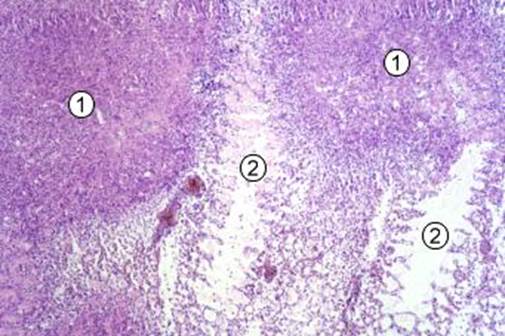

Рис. 31. Милиарная туберкулезная гранулема. В центре расположен участок казеозного некроза с обызвествлением (1 – участок обызвествленного казеозного некроза); 2 – зона эпителиоидных клеток; 3- гигантские клетки Пирогова-Лангханса; 4 – зона лимфоидных клеток, представленная лимфоцитами, плпзмоцитами; 5 – формирующаяся соединительнотканная капсула